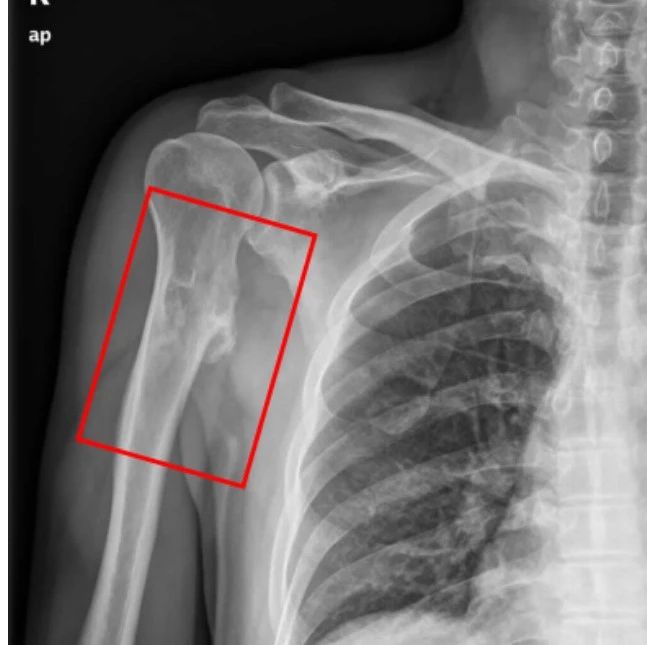

医学影像  yxyx-app  医学影像APP,打造伴随医生快速成长的影像学习社区。与影像园(Xctmr.com)一起提供最全面的影像案例库、基础(解剖、病理、影像诊断)知识、影像技术及考题等,为医生提供最佳的医学影像参考。【所属科室】骨科【基本资料】患者,男,30岁【主诉】左髋部酸胀半年【影像图片】【讨论问题】如何诊断?【医学影像APP用户讨论】评论:左髋关节周围见多发类圆形结节影,边界清,呈环状高密度,中央密度低。考虑滑膜骨软骨瘤病。...